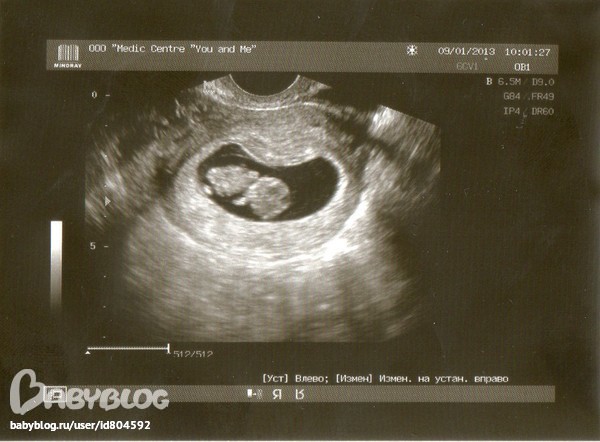

О боже)))))наконец-то.....я сегодня впервые увидела тебя...такой лапонька,такие рученьки,ноженьки)))Сердечко.

Врач сказала что всё соответствует сроку, малыш развивается хорошо)))Я так рада-когда его увидела-сразу поняла-он внутри меня-он наш-любимый,желанный)Наш хороший!

Срок- (матка увеличена соот-но сроку беременности 8.2 нед)

Средний диаметр 36 мм, соотв. 9.2 нед. берем.

Гипертонус миометрия- нет

Желточный мешок-5 мм

ЧСС эмбриона, уд/мин: 148

КТР:25 9.3 (8.6-10.1)

БПР:12 менее 11

Беременность 9.2 недельки!!!!Богатырь наш))))))Тьфу,тьфу,тьфу-чтобы всё в дальнейшем было хорошо и ты рос здоровеньким*